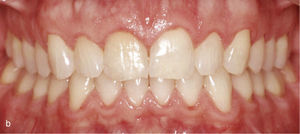

Con frecuencia los corredores vestibulares perjudican la apariencia estética al sonreír. Los dientes posteriores inclinados hacia palatino y hacia lingual «desaparecen» detrás de los dientes anteriores, de modo que la sonrisa se muestra acortada e incompleta (fig. 5a). Con el enderezamiento de los dientes posteriores combinado con una expansión se rellenan los corredores vestibulares y se completa la sonrisa (fig. 5b).